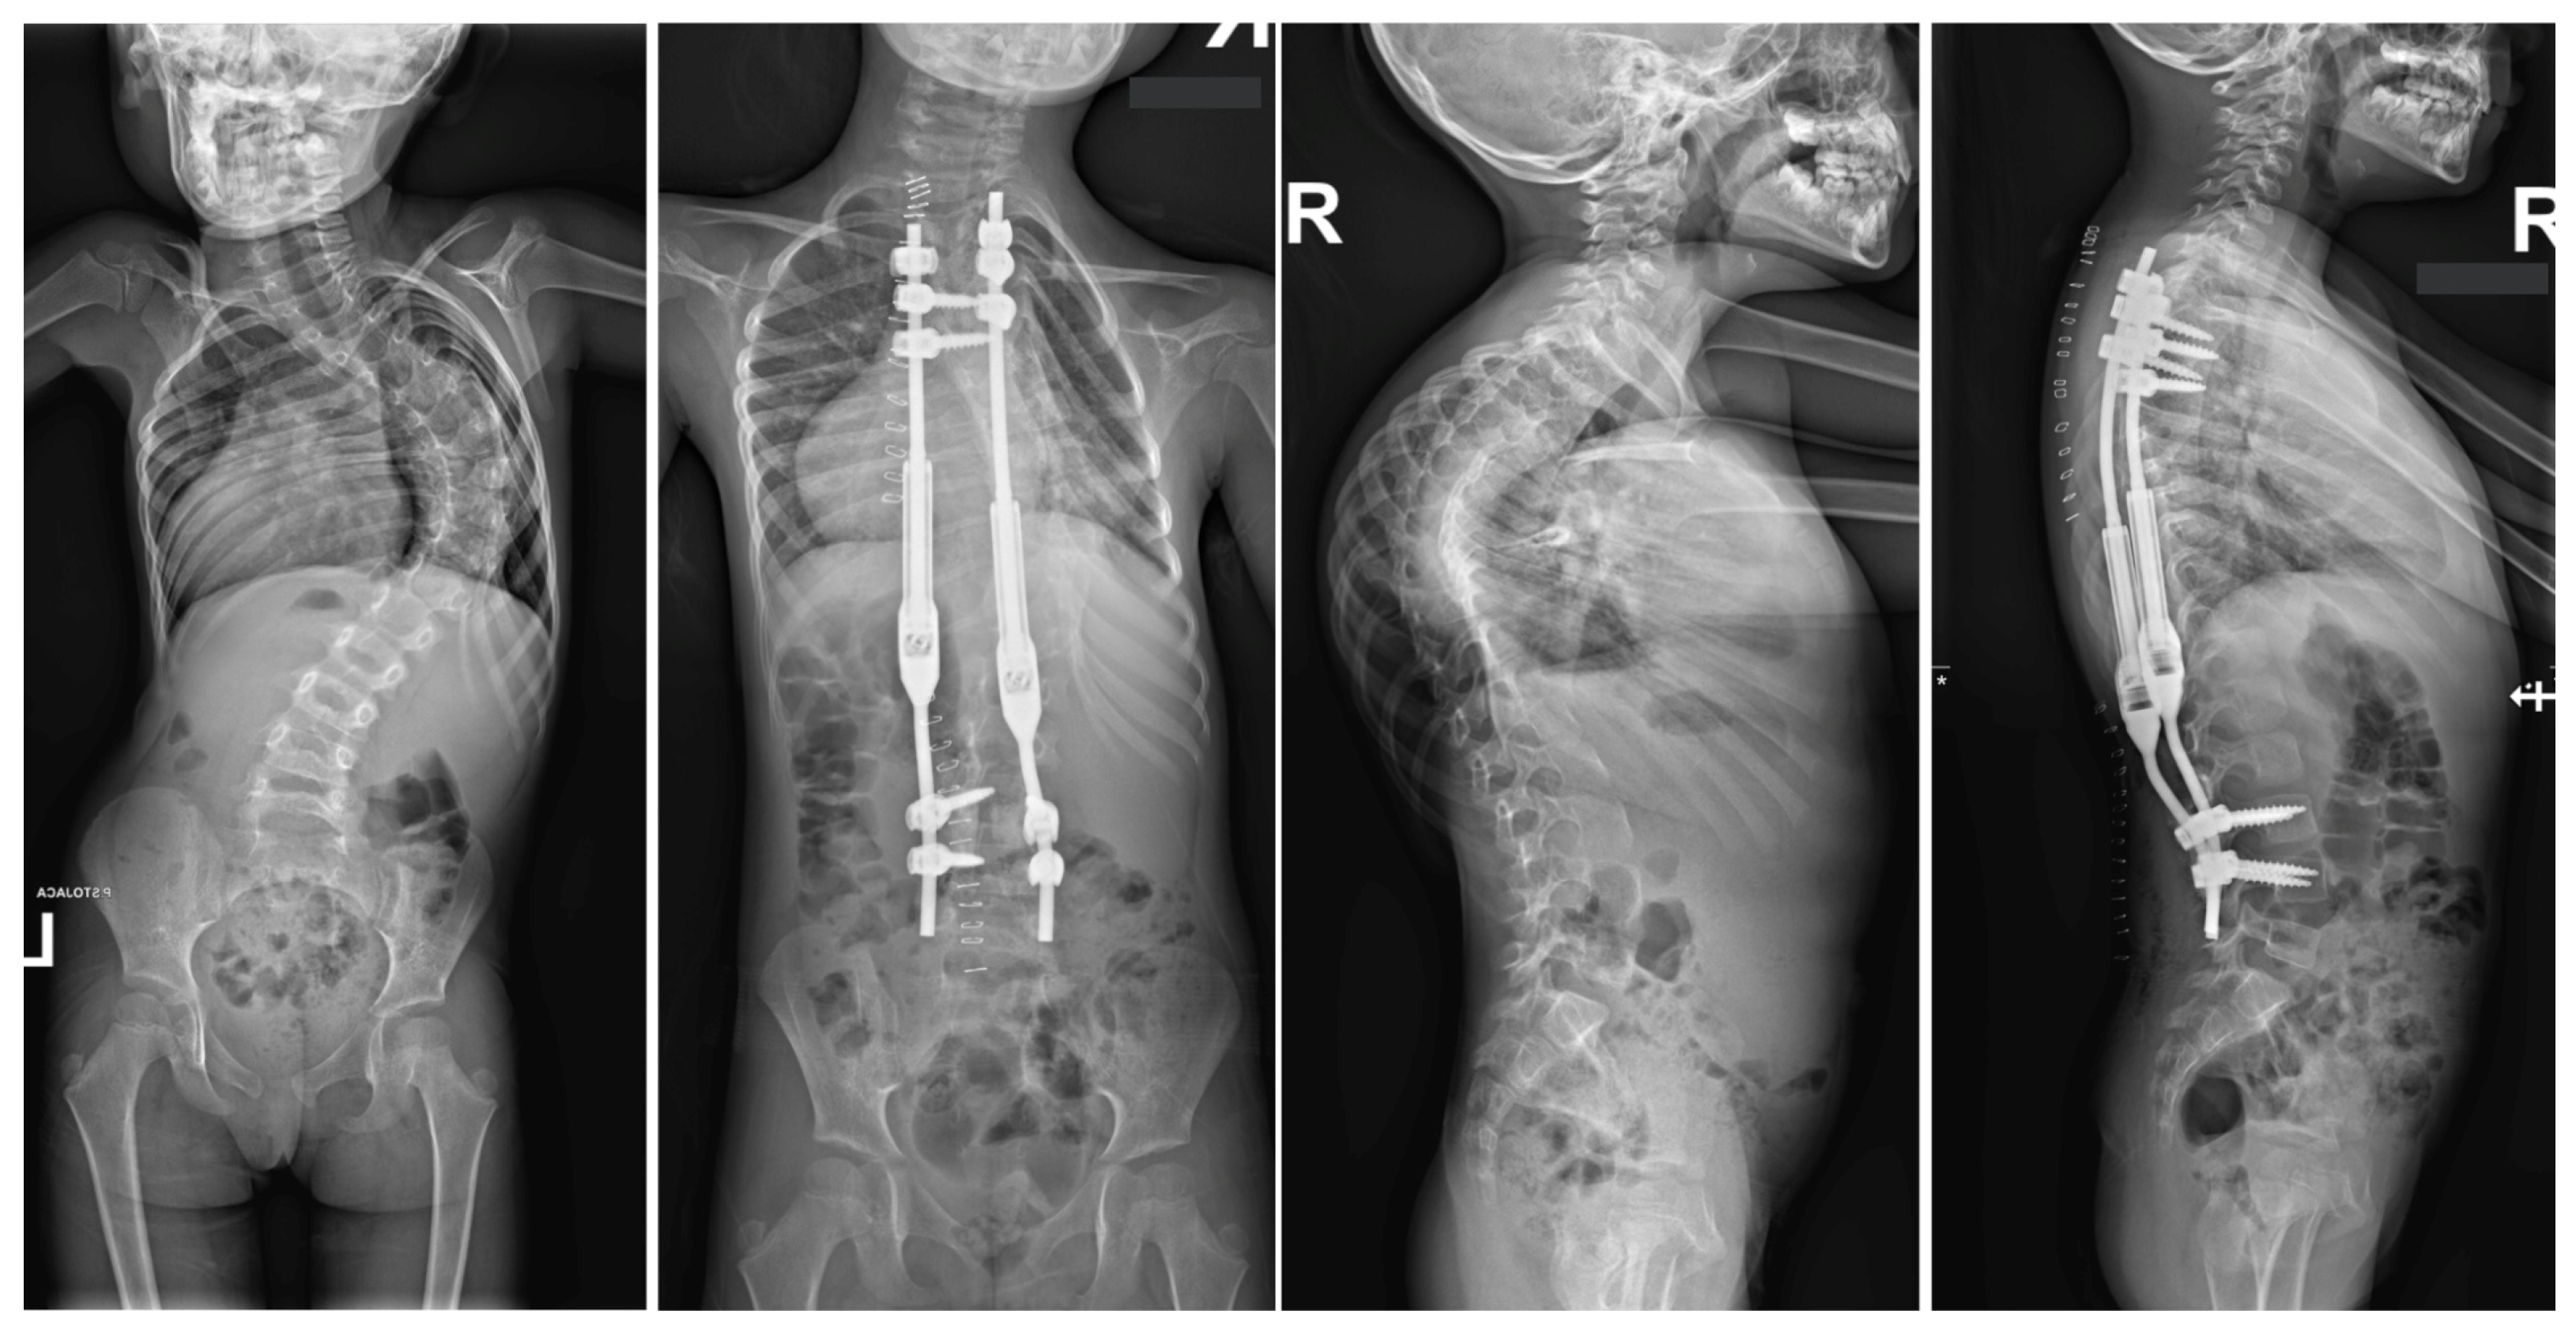

- Grabala, P.; Galgano, M.A.; Grabala, M.; Buchowski, J.M. Radiological and Pulmonary Results of Surgical Treatment of Severe Idiopathic Scoliosis Using Preoperative Halo Gravity Traction Compared with Less Invasive Temporary Internal Distraction in Staged Surgery in Adolescents. J. Clin. Med. 2024, 13, 2875. [Google Scholar] [CrossRef] [PubMed]

- Grabala, P.; Helenius, I.J.; Buchowski, J.M.; Shah, S.A. The Efficacy of a Posterior Approach to Surgical Correction for Neglected Idiopathic Scoliosis: A Comparative Analysis According to Health-Related Quality of Life, Pulmonary Function, Back Pain and Sexual Function. Children 2023, 10, 299. [Google Scholar] [CrossRef] [PubMed]

- Grabala, P.; Chamberlin, K.; Grabala, M.; Galgano, M.A.; Helenius, I.J. No Benefits in Using Magnetically Controlled Growing Rod as Temporary Internal Distraction Device in Staged Surgical Procedure for Management of Severe and Neglected Scoliosis in Adolescents. J. Clin. Med. 2023, 12, 5352. [Google Scholar] [CrossRef] [PubMed]

- Grabala, P.; Kowalski, P.; Rudziński, M.J.; Polis, B.; Grabala, M. The Surgical Management of Severe Scoliosis in Immature Patient with a Very Rare Disease Costello Syndrome-Clinical Example and Brief Literature Review. Life 2024, 14, 740. [Google Scholar] [CrossRef]

- Koller, H.; Mayer, M.; Koller, J.; Ferraris, L.; Wiedenhöfer, B.; Hitzl, W.; Hempfing, A. Temporary treatment with magnetically controlled growing rod for surgical correction of severe adolescent idiopathic thoracic scoliosis greater than 100°. Eur. Spine J. 2021, 30, 788–796. [Google Scholar] [CrossRef] [PubMed]